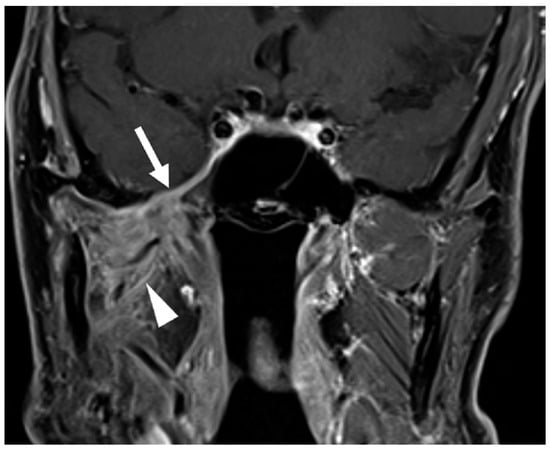

- Overfield, C.J.; Rhyner, P.A.; Hall, M.R.; Bhatt, A.A. More than Skin Deep: Imaging of Dermatologic Disease in the Head and Neck. RadioGraphics 2024, 44, e240052. [Google Scholar] [CrossRef] [PubMed]

- Agarwal, M.; Wangaryattawanich, P.; Rath, T.J. Perineural Tumor Spread in Head and Neck Malignancies. Semin. Roentgenol. 2019, 54, 258–275. [Google Scholar] [CrossRef]